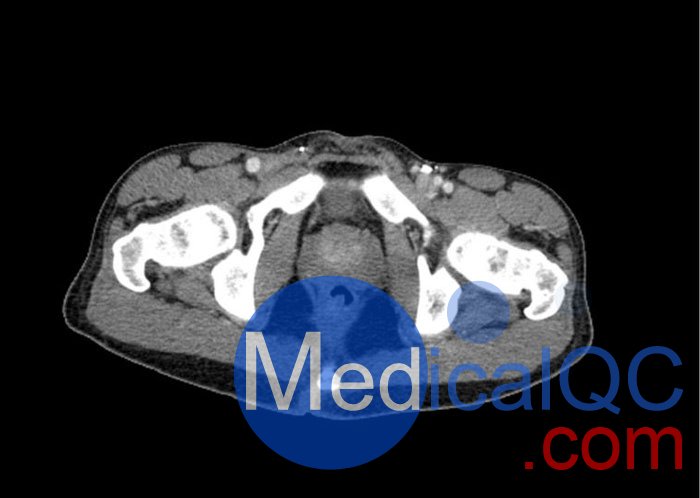

WEK57-01門靜脈期軀干模體,WEK57-01軀干模型模擬了門靜脈期的造影劑增強(qiáng)胸部、腹部和骨盆。它覆蓋了會陰的第二胸椎。

右側(cè)有髂淋巴結(jié)腫塊。

該模型可用于 CT(包括 CBCT)以評估和優(yōu)化成像性能和后處理應(yīng)用,包括支持 AI 的應(yīng)用。它也適用于培訓(xùn)目的。

該模型提供了對軟組織和骨組織的詳細(xì)而逼真的模擬。包括肺在內(nèi)的空隙充滿了大約 -160HU的纖維素聚合物復(fù)合材料。

真實模擬脈管系統(tǒng)、骨骼和軟組織,包括肺、心臟、肝臟、膽囊、胰腺、脾臟、腎上腺、腎臟、胃、小腸、結(jié)腸、膀胱和前列腺。

右側(cè)髂外淋巴結(jié)腫塊。

大?。?約 267 x 185 x 466 mm

重量: 約 11040 g

基材: 纖維素-聚合物復(fù)合材料

最佳管電壓: 120 kVp – 可根據(jù)要求進(jìn)行調(diào)整

WEK57-01門靜脈期軀干模體,WEK57-01軀干模型成像效果圖: